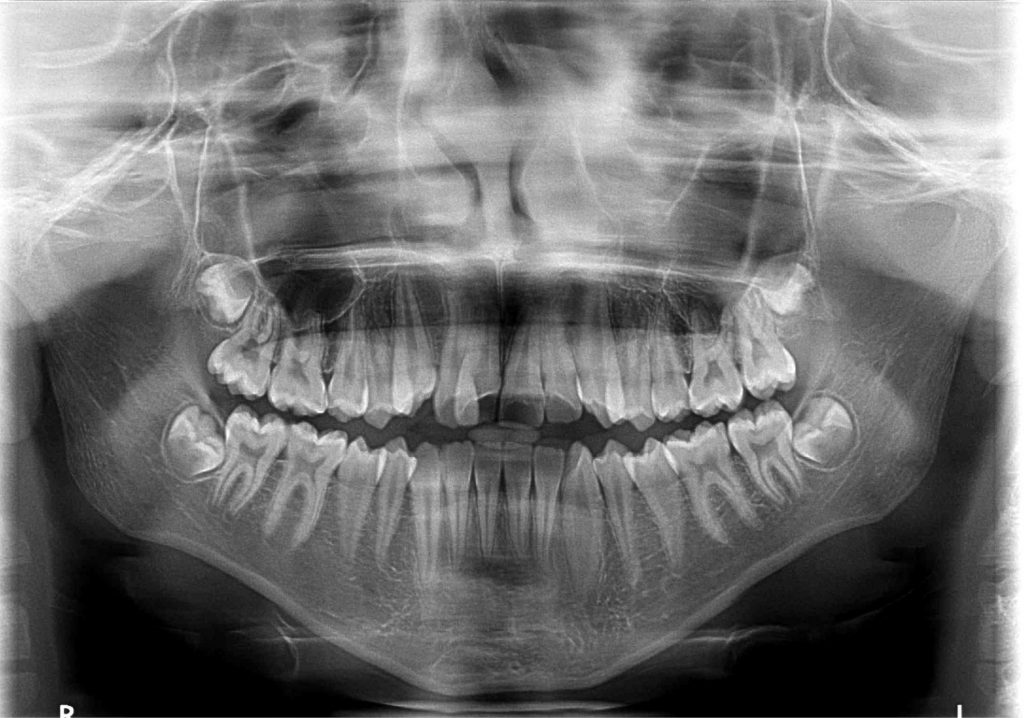

Streszczenie: W pracy omówiono leczenie rosnącego pacjenta z wadą szkieletową klasy III oraz jednostronnym zgryzem krzyżowym prawostronnym. Leczenie ortodontyczne polegało w pierwszym etapie na poszerzeniu szczęki za pomocą aparatu hyrax oraz jej protrakcji za pomocą maski twarzowej. Następnie założono aparat stały w łuku górnym i dolnym. Po uzyskaniu klasy I wg Angle’a zdemontowano aparat stały. Do momentu ukończenia wzrostu pacjenta planowana jest obserwacja zgryzu. Jeżeli dojdzie do nawrotu wady, planowana jest operacja ortognatyczna.

Summary: The paper discusses the treatment of a growing patient with a class III malocclusion and right-sided crossbite. In the first step, orthodontic treatment based on widening the jaw with a hyrax and its protraction with a facemask was introduced. Then a fixed appliance was used in the upper and lower arch. After obtaining class I according to Angle, the fixed appaliance was removed. Observation of the bite is planned until the completion of the patient’s growth. If the malocclusion returns, orthognathic surgery is planned.